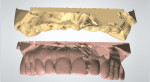

The cast of the immediate-load hybrid prosthesis was scanned (Figure 9). The opposing cast was scanned, and the three scanned casts were merged (Figure 10). Using the superimposed scan of the immediate-load prosthesis as a guide, library teeth from the database in the CAD system were selected and placed in their appropriate locations. Connectors, screw-access holes, and gingival tissues were designed (Figure 11). Once the design was finalized, the design file was sent to the CAM workstation where it was nested in a polymethyl methacrylate (PMMA) block. The CAM software computed the tool path for the milling machine, and a PMMA replica of the final restoration was milled. Metal interfaces were cemented into the PMMA replica and it was returned for try-in (Figure 12).

The main function of the PMMA replica is to verify the esthetics, function, and occlusion intraorally. If needed, the PMMA replica can be modified and the occlusion adjusted, and the replica can even be worn by the patient for a short period of time if desired (Figure 13). When all manual adjustments were completed, the PMMA could be rescanned and the adjustments transferred to the digital design.

The most common post-treatment complication of a porcelain-fused-to-zirconia restoration is porcelain chipping.12,13 In this case, all of the occluding surfaces were to be in zirconia, while the labial aspect of the six anterior teeth were to be layered feldspathic porcelain. This would decrease the chance that occlusal forces would cause porcelain chipping. This cut-back was accomplished in the design software, which thus completed the design process. The final digital design was transferred to the CAM workstation where it was nested in a zirconia block (Ceramill® zolid, Amann Girrbach AG, www.amanngirrbach.com) and then milled (Figure 14). The zirconia block was in a pre-sintered or “green” state. Fine detail was then carved into the milled zirconia block using diamond burs, diamond discs, and hand instruments.